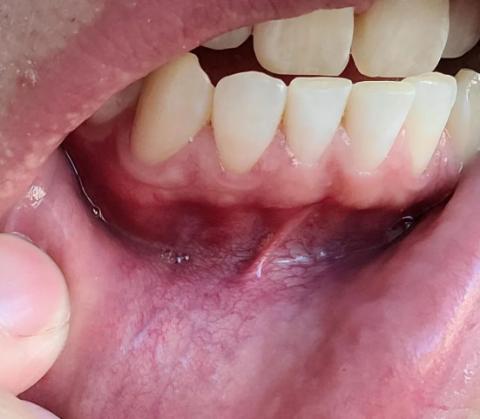

Focused Area: Lower anterior teeth (lingual side) and gingival tissue

Observed Conditions

Visible dental calculus (tartar) accumulation along the gumline, especially behind the lower front teeth

Gingival redness and mild swelling consistent with inflammation

Possible early gum recession in localized areas

No obvious carious lesions visible, though calculus may conceal decay without radiographic examination

Probable Diagnosis

Plaque-induced gingivitis

Moderate dental calculus buildup

Risk of early periodontal disease if untreated